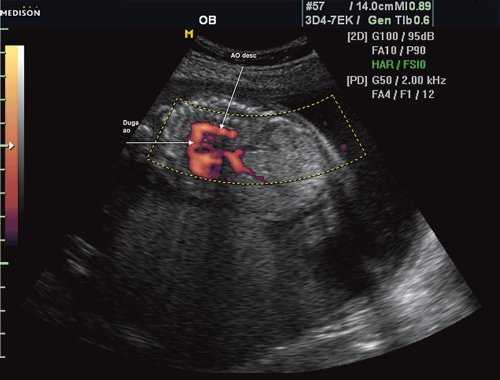

Первая причина не диагностированной коарктации аорты это морфогенез патологии и теория первичного нарушения развития дуги аорты. Теория была предложена в 1828 г. [11]. Автор считает, что данная патология связана с недостаточным соединением 4 и 6 дуги аорты с нисходящим ее отделом. Поэтому перешеек - это место, где наиболее часто локализуется участок сужения [12], так как оба отдела образуются из разных эмбриональных зачатков. В норме область перешейка аорты равна 2/3 диаметра восходящего отдела аорты (рис. 1).

Рис. 1. Восходящий отдел, дуга и нисходящий отдел аорты плода в режиме энергетического допплера в норме.

Согласно "теории дуктальной ткани" коарктация аорты возникает в результате миграции гладких мышечных клеток протока в предуктальную аорту, с последующей констрикцией и сужением просвета аорты [4]. При формировании коарктации аорты в области перешейка сохраняется сужение различной протяженности и формы (рис. 2, 3). Наиболее часто это проявляется в виде локальной перетяжки, выше или ниже которой диаметр аорты сохраняется в норме.

Рис. 2. Ультразвуковое исследование восходящего отдела, дуги и нисходящего отдела аорты. Стрелкой указано место сужения.